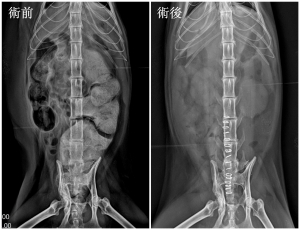

從 X 光上可以看到,喵喵的結腸已經被糞便塞到比正常大了兩倍以上 !更進一步檢查還發現牠有 骨盆狹窄 的問題,這很可能就是導致 巨結腸症(megacolon) 的主因。

在綜合評估後,為了提升喵喵的生活品質,我們安排手術,把已經失去功能的結腸段切除,再把健康的結腸和直腸重新接起來。

好消息是 手術後喵喵恢復得很好,食慾大增,每天正常排便,精神也好多了!主人說牠現在眼神都亮晶晶的,整隻貓都變得更快樂、更可愛啦